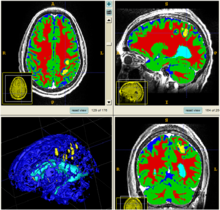

Experiments: Multi-modal registration and tissue segmentation

We conducted experiments with the application of the ABC tool to multi-modal image data of 5 TBI cases provided by DBP partner UCLA. The tool includes co-registration of multiple modalities via mutual-information linear registration, and a nonlinear registration (high-deformable fluid registration) of a probabilistic normative atlas for segmentation of healthy tissue. The following results show feasibility of multi-modal registration and segmentation of normal tissue. Pathology is segmented via postprocessing using 3D user-supervised level-set evolution.

Case 1: Segmentation of 5channel TBI data with ABC. Lesions and ventricles segmented with additional 3D level-set segmentation.

Case 2: Segmentation of 5channel TBI data with ABC. Lesions and ventricles segmented with additional 3D level-set segmentation.

Case 3: Segmentation of 5channel TBI data with ABC. Lesions and ventricles segmented with additional 3D level-set segmentation.